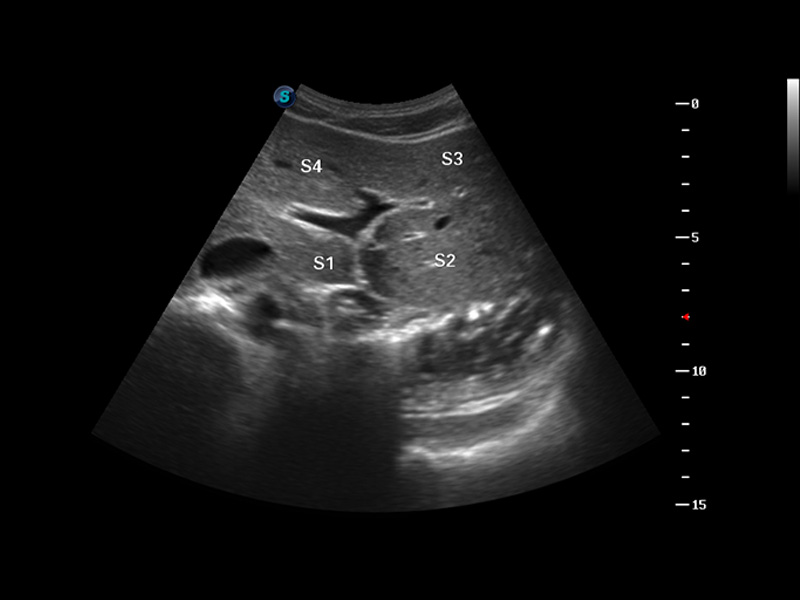

μ-Scan微米成像

空间复合成像